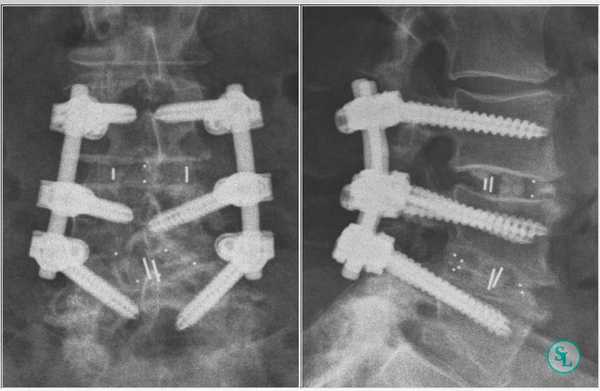

Дискэктомия (удаление разрушенного диска) и корпэктомия (удаление фрагмента тела позвонка) позволяют полностью очистить пораженные ткани. Внедрение распорочных трансплантатов (вырезанных из костных структур, взятых в ребрах или гребне подвздошной кости) позволяет хрящевым тканям начать восстанавливаться, а фиксирующие позвоночный столб титановые конструкции временно снимут нагрузку на пострадавшие позвонки. Реабилитация занимает от 3 месяцев до полугода. Прогноз на излечение спондилодисцита всегда положителен.

Чтобы иммобилизация позвоночно-двигательного сегмента была максимально надежной, нередко операция дополняется выполнением транспедикулярной фиксации. В таком случае устанавливаются специальные металлические конструкции, которые еще более упрочняют скрепление тел позвонков.

Дискэктомия (удаление разрушенного диска) и корпэктомия (удаление фрагмента тела позвонка) позволяют полностью очистить пораженные ткани. Внедрение распорочных трансплантатов (вырезанных из костных структур, взятых в ребрах или гребне подвздошной кости) позволяет хрящевым тканям начать восстанавливаться, а фиксирующие позвоночный столб титановые конструкции временно снимут нагрузку на пострадавшие позвонки. Реабилитация занимает от 3 месяцев до полугода.